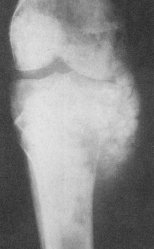

ABCESUL BRODIE se localizeaza la nivelul epifizelor oaselor lungi - mai ales în epifiza distala a femurului sau proximala a tibiei; se caracterizeaza printr-o zona de osteoliza bine delimitata de o zona de osteoscleroza.